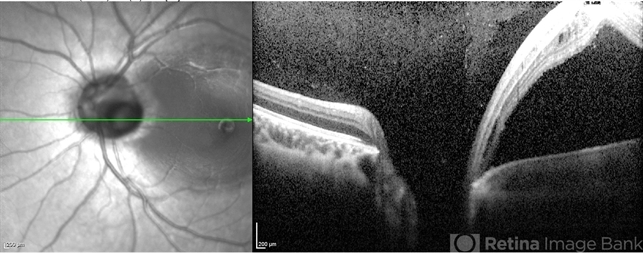

- maculopathy, optical coherence tomography (OCT)

Optical coherence tomography system

Heidelberg Spectralis - Description

- 10-year-old girl with congenital optic pit and recent vision loss secondary to optic pit maculopathy.